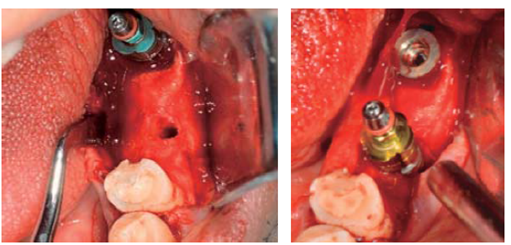

Se coloca implante marca BTI® en zona de 36 de 5 x 11.5 mm, torqueado a 40 N, e implante inmediato a la extracción, en zona de 37 de 5.5 x 13 mm con torque de 30 N (Figura 14).

Se efectuó regeneración ósea mediante colocación de membrana de colágeno y combinación de hueso autólogo colectado con protocolo de fresado biológico a 50 rpm acompañado de aloinjerto óseo de la marca Biograft® de 500 a 800 μm de partícula.5

Se colocaron tornillos tapa y consiguiendo cierre sin tensión del colgajo, se suturó con seda 4Ø. Se prosigue a la provisionalización de los implantes previo descubrimiento (Figura 15).

Alcanzada esta etapa del tratamiento, se prosiguió con la planeación y colocación de implantes en zona de 14 y 16 de la marca Hiossen™ de 4 x 10 mm. La guía utilizada fue permisiva, los implantes consiguieron una estabilidad primaria de 30 N y ambos lechos fueron regenerados con 1 cm3 de aloinjerto óseo Biograft® y membrana de colágena RCM6® (Figuras 29a31).